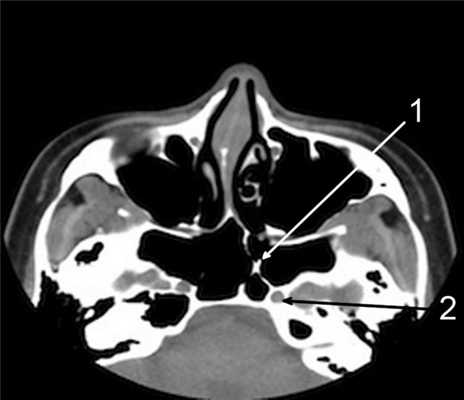

д) наличие супраорбитальных клеток решетчатого лабиринта, степень их пневматизации, расположение относительно лобного кармана (рис. 9); Рисунок 9. Супраорбитальные клетки решетчатого лабиринта. КТ, аксиальная проекция. Видны лобные пазухи (ЛП) и супраорбитальные клетки (СОК) решетчатого лабиринта с двух сторон.

е) наличие пневматизации перегородки между лобными пазухами [1, 15].